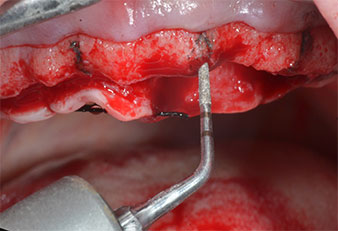

Ein flammenförmiges, diamantiertes piezochirurgisches Instrument (Piezomed I1) wurde verwendet, um die Implantatpositionen zu markieren und die Pilotpräparationen durchzuführen (Abb. 3). Dabei wurde darauf geachtet, eine Auf- und Abbewegung mit reduzierter Leistung, voller Spülung und niedrigem Druck (unter 300 g) anzuwenden. Als Nächstes wurde ein Pilotinstrument (Piezomed I2A/I2P) zur initialen Erweiterung der Implantatlager auf einen Durchmesser von 2 mm verwendet (Abb. 4), gefolgt von einem 3-mm-Instrument (Abb. 5).

Chirurgisches Instrument Piezomed

Abb. 4: Der nächste Schritt ist die initiale Erweiterung mit den Instrumenten Piezomed I2A/I2P, die in einer horizontalen Drehbewegung verwendet werden.